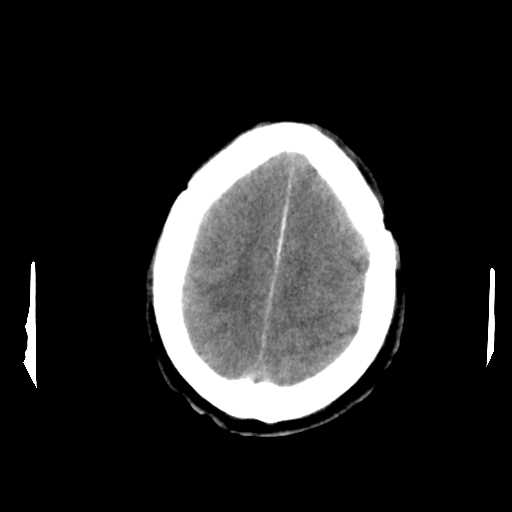

Figure 2: Examples of CT scan slices that were removed during preprocessing. These slices were eliminated because of lack of relevant brain tissue, or poor image quality, ensuring that only the most informative slices contribute to the classification process.

Slices from CT scan images that lacked relevant diagnostic information were manually removed, as illustrated in Fig. 2. This process excluded slices with missing brain tissue or poor image quality, ensuring that only the most informative and clinically relevant scans were used for classification. Following this initial filtering step, additional preprocessing was applied to further refine the dataset.